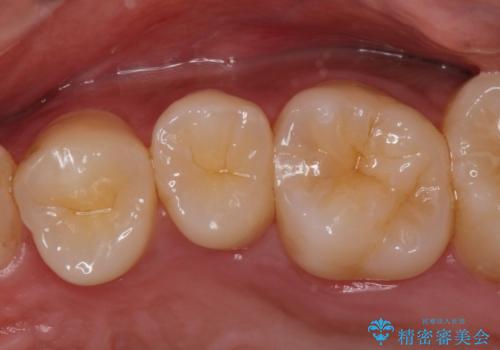

- ジルコニアクラウン(スペシャル)・ 仮歯 16.5万円×3 費用は治療当時の料金となります

適合が良い被せ物が入りました。

隙間がなく被せ物が入ることによりう蝕の再発のリスクが低くなります。